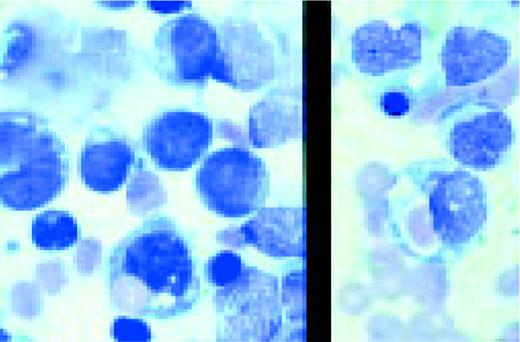

Prolymphocytic leukemia (PLL). This composite slide shows prolymphocytic leukemia (PLL) from two different patients. On the left is B cell PLL and on the right, T cell PLL. The B-PLL cells correspond to the classic description of Galton et al. (Br J Haematol 27:7, 1974): They are larger than CLL lymphocytes, have condensed chromatin, and have prominent large nucleoli. The T-PLL cells have a less conspicuous nucleolus, an irregular nuclear outline, and cytoplasmic blebs, as described by Matutes et al. (Blood 78:12, 1991). In many cases it may (FIX) be difficult to distinguish B-PLL from T-PLL cells on morphologic grounds alone, without performing additional immunophenotypic studies.FIG14